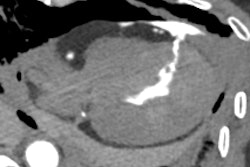

A 67-year-old patient was brought to the emergency department after severe trauma. The CT scan of the encephalon shows a left occipital fracture with extension to the petrous portion of the ipsilateral temporalis (longitudinal type). CT angiography of the cerebral arteries reveals early repletion of the arterial phase of the left superior ophthalmic vein, as well as several hyperdense foci in the left cavernous sinus (circle), indicative of a carotid-cavernous fistula. All figures courtesy of Dr. César Antonio López López et al and presented at ECR 2025.

“In these cases, it is important to describe the type of fracture, if there is herniation of the orbital fat through the fracture or if there is entrapment of the extraocular muscles, as well as to evaluate possible eye involvement (breakage, hematomas, foreign bodies ...),” noted López, adding that other post-traumatic findings to rule out include carotid-cavernous fistula.

Carotid-cavernous fistula is an abnormal communication between the carotid circulation and the cavernous sinus. It can be classified as direct (direct communication between the internal carotid and cavernous sinus) or indirect (communication through one of the branches of the carotid circulation and the cavernous sinus). Direct communication tends to be post-traumatic and of rapid evolution, tending to be found in young men. Indirect communication is usually insidious, secondary to predisposing conditions (Ehlers-Danlos Syndrome, for example), and in postmenopausal women.

“On CT we can see indirect findings such as proptosis, edema of the orbital fat, enlargement of the extraocular musculature, as well as swelling of the cavernous sinus and arterial enhancement of the ophthalmic vein and the cavernous sinus,” they stated. “It is important to suspect this pathology in certain traumas, as it is important to diagnose it because of possible complications.”